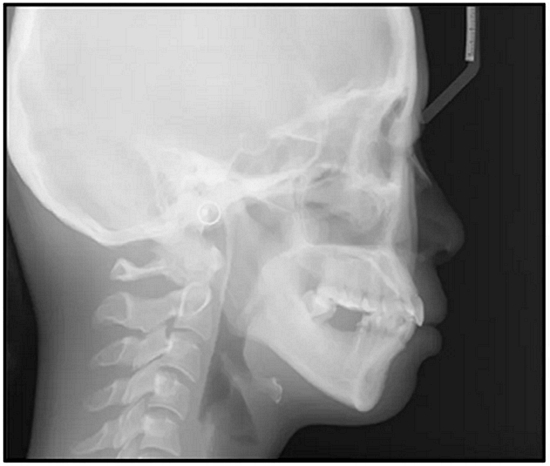

36歲;女性;尋求下頜左后方區(qū)域間隙管理的建議(圖1和圖2),通過治療獲得了良好的牙頜面效果(圖3和圖4)。她被診斷患有骨性I類和代償性牙性II類錯合畸形,并且上頜左側(cè)尖牙缺失(圖1和2)。大約七年前,由于不可修復(fù)的齲齒,拔除了下頜左側(cè)第一和第二磨牙(圖5)。37相鄰的第三磨牙向近中移動并傾斜入間隙,導致無牙頜間隙減小至約14 mm(圖2和圖5)。臨床和影像學評估顯示多發(fā)性齲損和在下頜右側(cè)567處有一不良的固定橋修復(fù)體(圖1和5)。此外,下頜左中切牙缺失,造成下頜中線向左側(cè)偏移約3 mm(圖1和圖2)?;颊咦栽V,她的右上第一前磨牙和左上尖牙在13歲時由其家庭牙醫(yī)拔除,因為它們被阻塞到頰側(cè)萌出(圖1)。上頜第二磨牙缺失(未知病因),并且相鄰的第三磨牙已經(jīng)轉(zhuǎn)移到第二磨牙間隙中。如補充材料所示,美國正畸學差異指數(shù)DI是28分。種植體部位(下頜左側(cè)和右側(cè)第一磨牙)由于復(fù)雜性得到額外4分(補充材料)。

總之,這種復(fù)合錯合畸形是一個很嚴重的問題,需要進行認真的多學科序列治療。治療后X光片(圖6)和重疊頭影測量圖(圖7)記錄了跨學科治療結(jié)果。

圖5. 治療前的側(cè)位片(上圖)和全景(下圖)的X光片